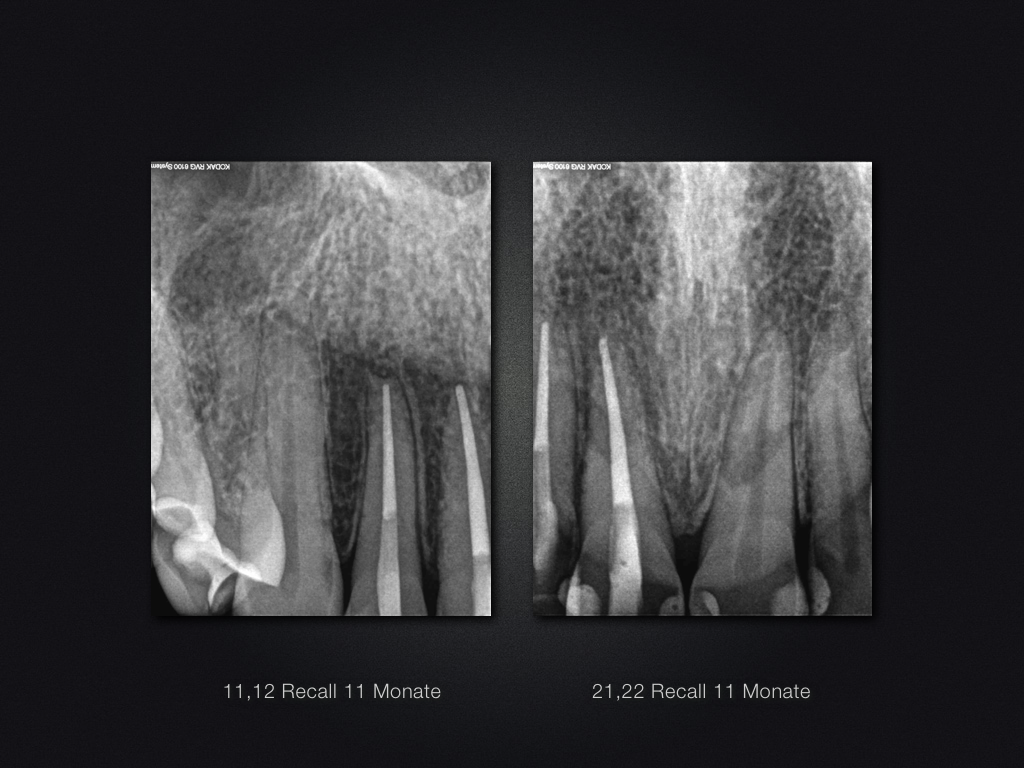

11 21 D.015

Recall nach Frontzahntrauma